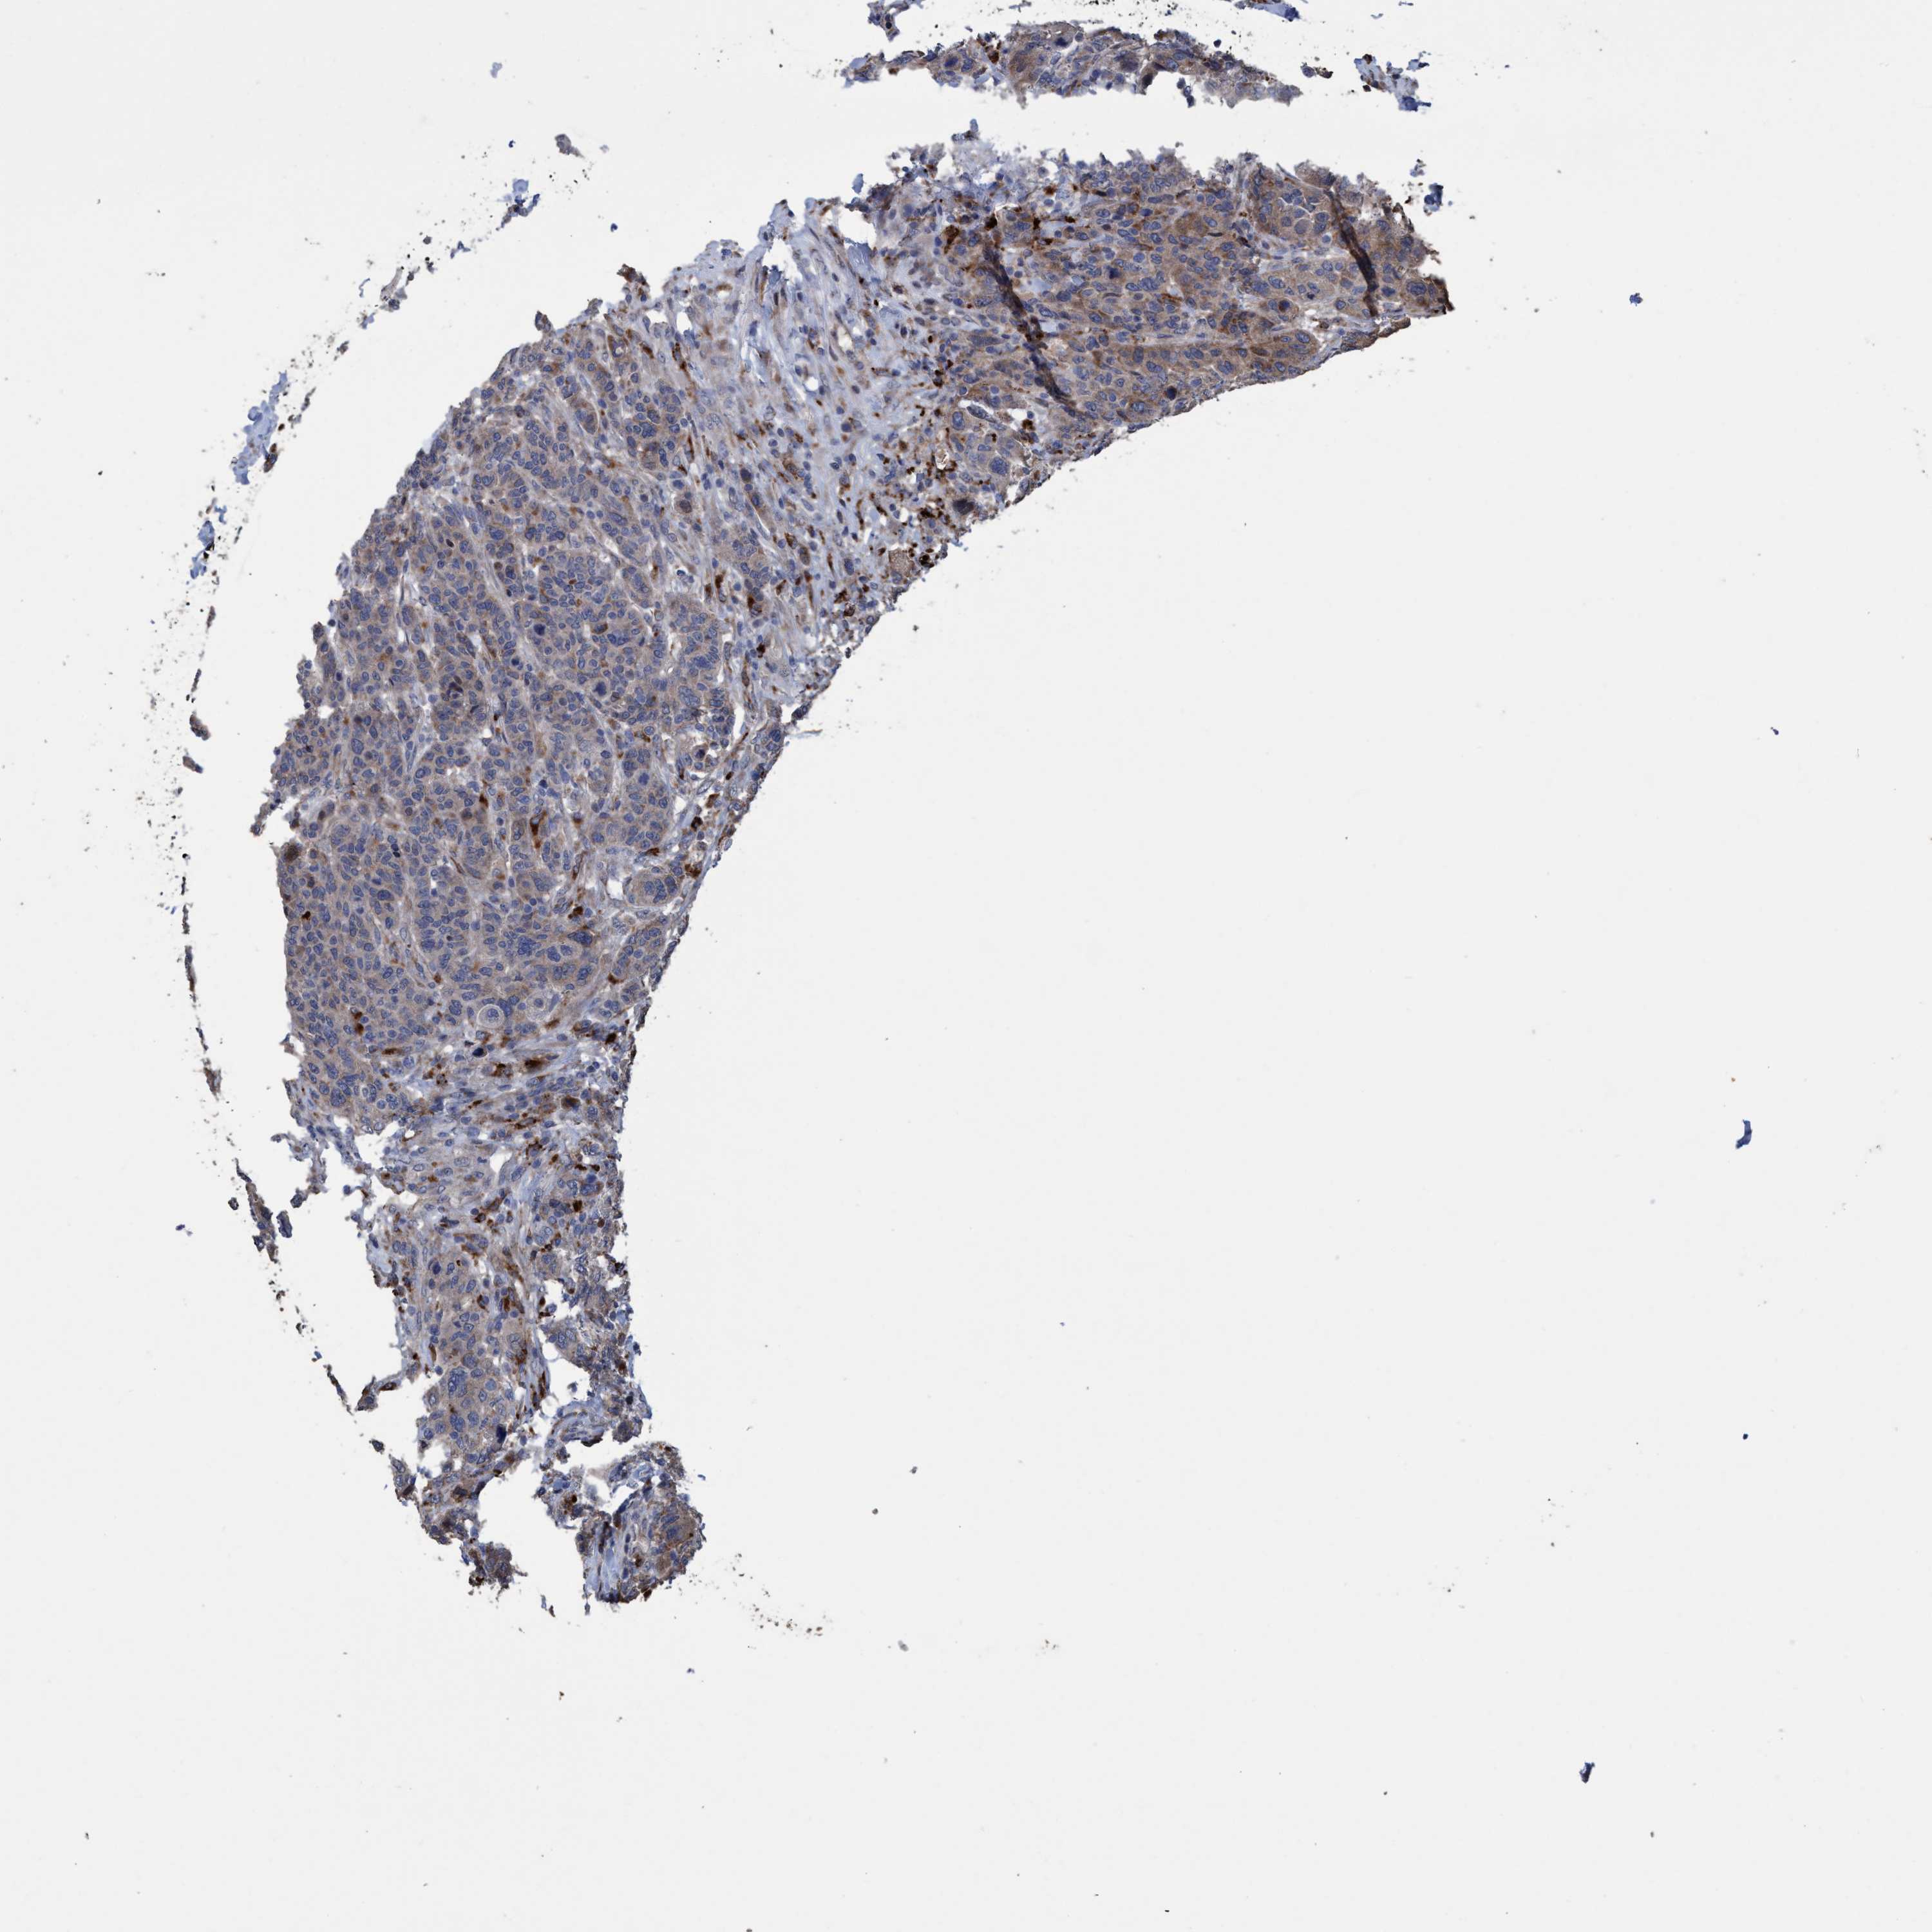

CANCER BREAST CANCER Show tissue menu

BRCA TCGA BRCA VALIDATION PROTEIN EXPRESSION

ANTIBODIES

AND

VALIDATION